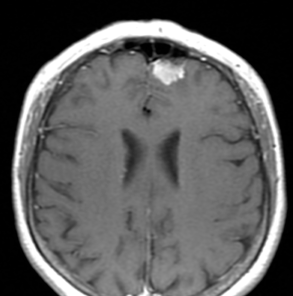

That's my tumor before it was evicted!

A meningioma is a type of tumor that develops from the meninges, the membrane that surrounds the brain and spinal cord. There are three layers of meninges, called the dura mater, arachnoid and pia mater. Most meningiomas (90 percent) are categorized as benign tumors, with the remaining 10 percent being atypical or malignant. However, the word benign can be misleading in this case, as when benign tumors grow and constrict and affect the brain, they can cause disability and even be life threatening.

Meningioma is the most common type of primary brain tumor, accounting for approximately 30% of all brain tumors. Meningiomas originate in the meninges, which are the outer three layers of tissue between the skull and the brain that cover and protect the brain just under the skull. Meningiomas grow out of the middle layer of the meninges, called the arachnoid. When they grow, they press against the brain or spinal cord.

No foreign matter, "benign" or not, belongs in your brain.